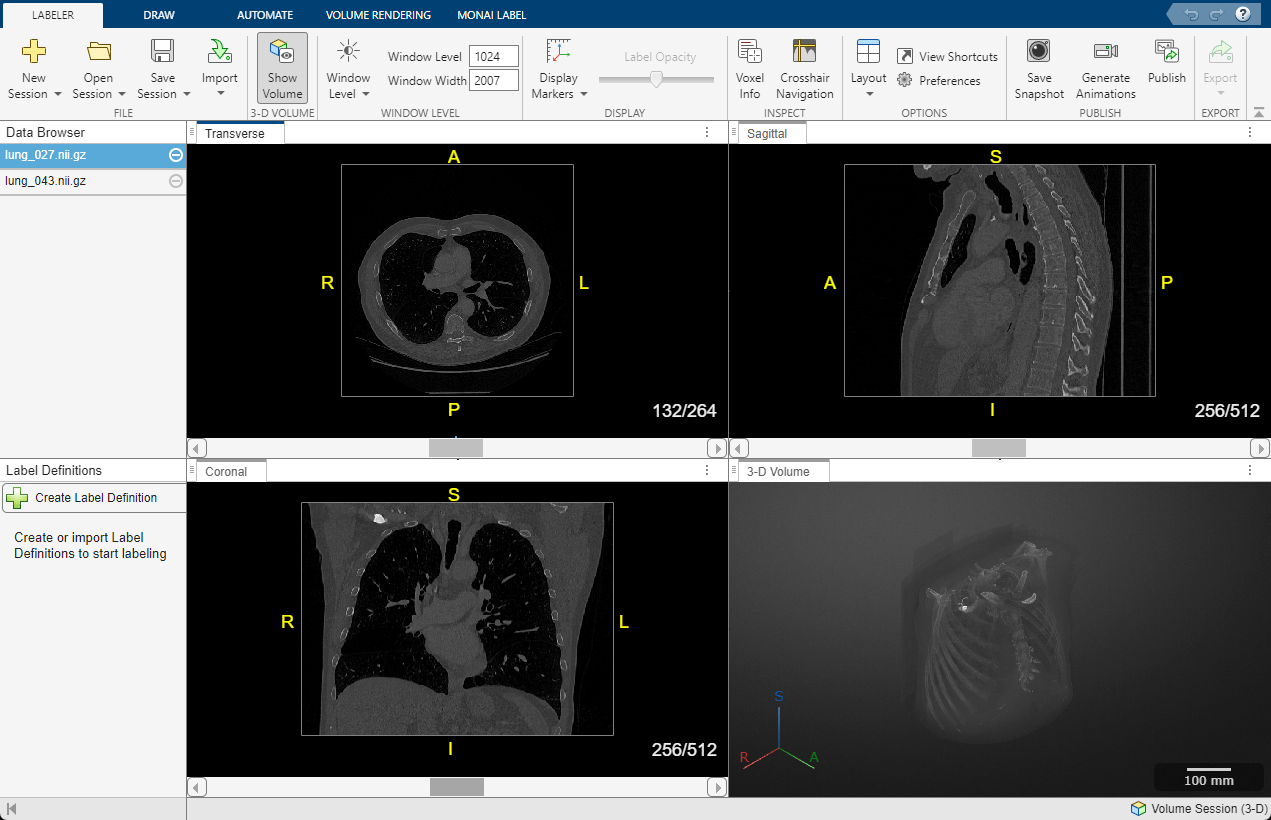

The Medical Image Labeler app displays a 3-D rendering of the scan in the 3-D Volume pane, and displays anatomical slice planes in the Transverse, Sagittal, and Coronal panes. You can toggle the visibility of the volume display using the Show Volume button on the Labeler tab of the app toolstrip.

By default, the app displays the center slice in each slice plane. You can change which slice is displayed by using the scroll bar at the bottom of a slice pane, or you can click the pane and then press the left and right arrow keys. The app displays the current slice number out of the total number of slices, such as 132/264, for each slice pane. The app also displays anatomical display markers indicating the anterior (A), posterior (P), left (L), right (R), superior (S), and inferior (I) directions. You can zoom in on the current slice pane using the mouse scroll wheel or the zoom controls that appear when you pause on the slice pane.